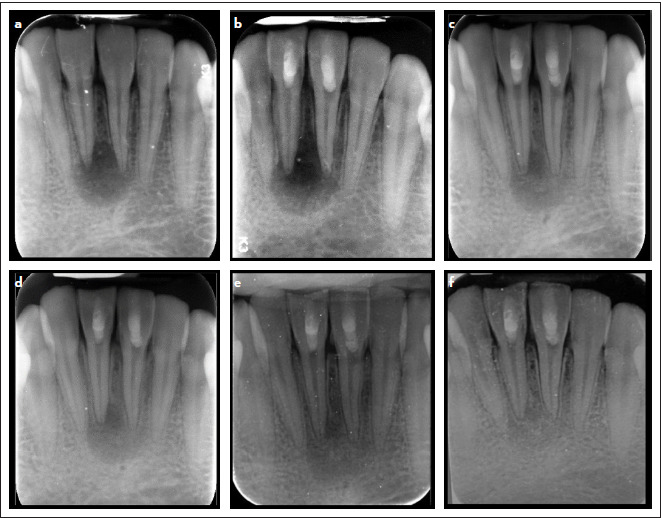

研究目的本随机对照研究旨在评估 Biodentine 与 MTA 相比,在牙髓坏死和根尖牙周炎的成熟单冠恒牙再生治疗后,Biodentine 作为牙髓间隙屏障在愈合根尖周病变和恢复牙髓敏感性方面的有效性:研究涉及 36 名患有牙髓坏死和根尖牙周炎的成熟牙齿患者。患者接受了利用血凝块技术的再生治疗。牙齿被随机分配到干预组(Biodentine)(18 个)或对照组(MTA)(18 个)。在长达 18 个月的随访中,对根尖周病变的愈合情况和牙齿的敏感性进行评估:研究分析了 31 名患者,其中生物素组和 MTA 组分别有两名和三名患者失去了随访机会。18 个月后,两组患者的根周病变均有效愈合;31 例患者中有 21 例(67.7%)愈合,10 例(32.3%)愈合,无失败病例。两组之间无明显差异(P=1.00)。超过 70% 的患者(31 位患者中的 22 位)恢复了牙齿的敏感性,各组间无统计学差异(P=0.703):结论:使用 MTA 或 Biodentine 血凝块进行再生治疗可有效解决根尖周病变,并恢复成熟牙齿的敏感性。

Methods: The study involved 36 patients with mature teeth with necrotic pulp and apical periodontitis. The patient underwent a regenerative treatment that utilized the blood clot technique. Teeth were randomly allocated to either the intervention, Biodentine, group (n=18) or the control, MTA, group (n=18). The healing of periapical lesions and tooth sensibility were evaluated throughout follow-up visits for up to 18 months.

Results: The study analyzed 31 patients; two patients within the biodentine group and three in the MTA group were lost to follow-up. After 18 months, both groups showed effective healing of periradicular lesions; 21 out of 31 patients (67.7%) were healed, ten patients (32.3%) were healing, and no failure cases occurred. There were no significant differences between the groups (p=1.00). More than 70% (22 out of 31 patients) regained their sensibility in their teeth, and the groups had no statistically significant difference (p=0.703).

Conclusion: Regenerative treatment using blood clots with either MTA or Biodentine effectively resolved periapical lesions and regained the sensibility of mature teeth.